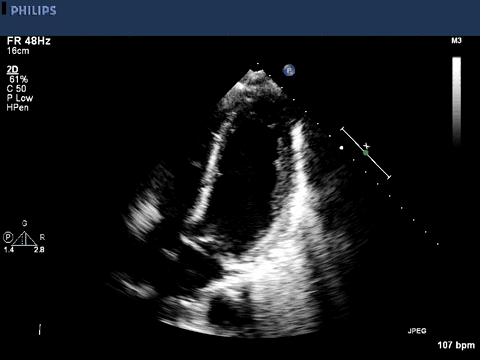

A transthoracic echocardiogram was obtained.